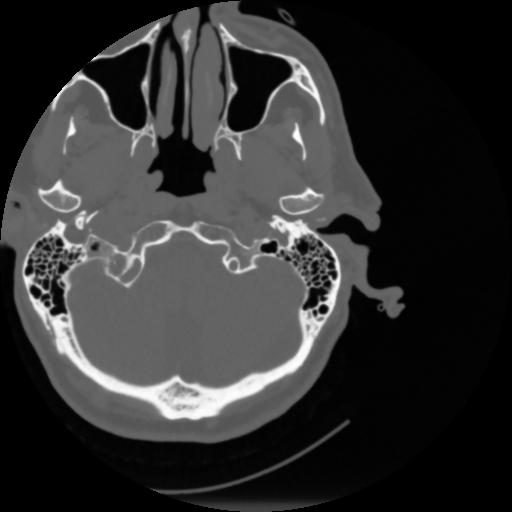

4 CEREBRO,,Vol,0.5,CEREBRO,,